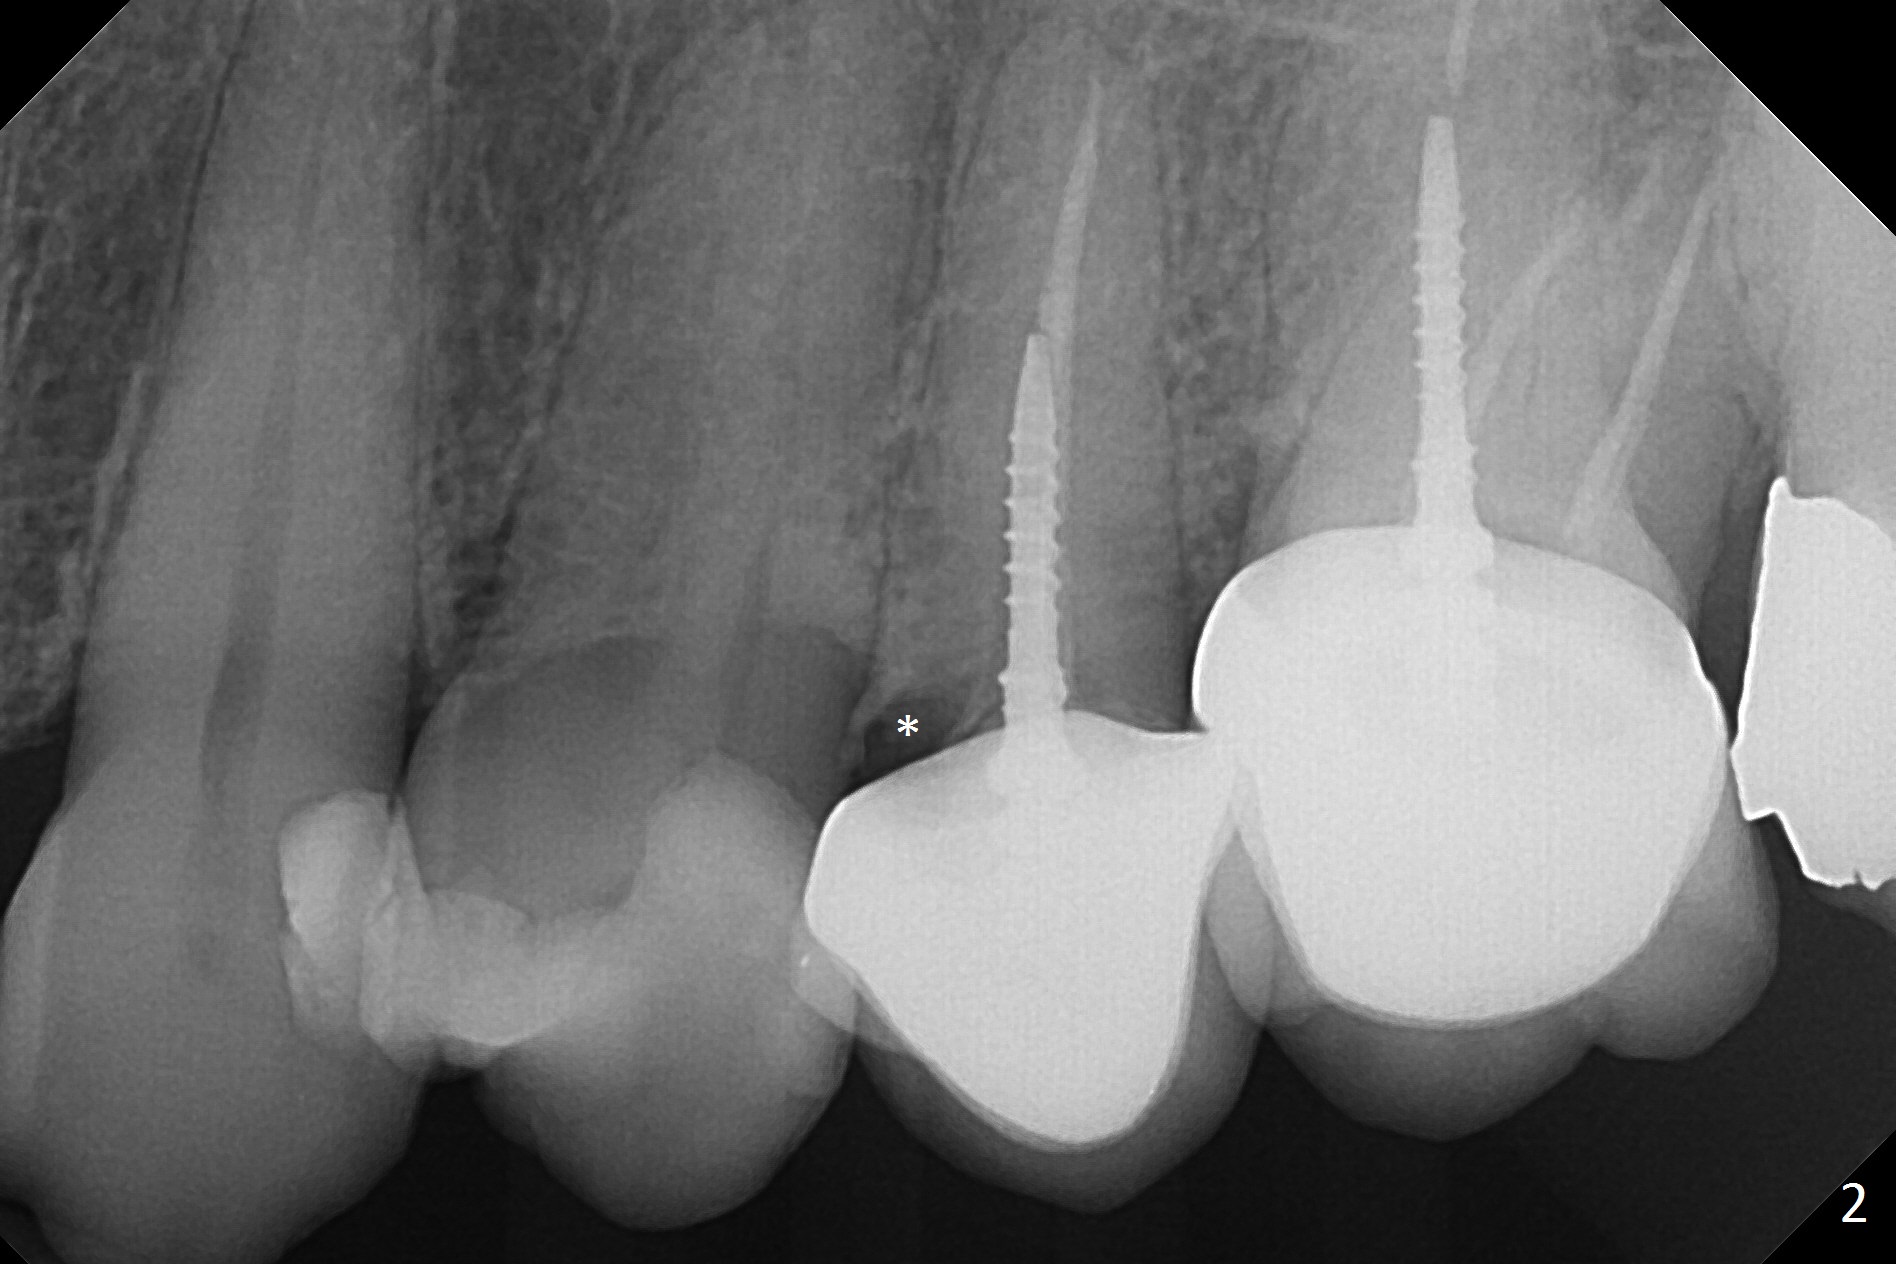

A 60-year-old woman returns to office with chief complaint "upper left crown is loose again". Clinical exam confirms #13 crown fracture at the gingival level (Fig.1,2 *). Since the native bone is short, an implant (Fig.3 green) should penetrate the sinus floor for primary stability. To protect the sinus membrane, PRF membranes (purple curved line) will be inserted prior to bone graft (red circles) and the implant. A pair abutment is expected to be 5x5 (5.7 exactly, blue) (Fig.3, pink) mm. The implant should be placed palatally to avoid buccal metal show through.